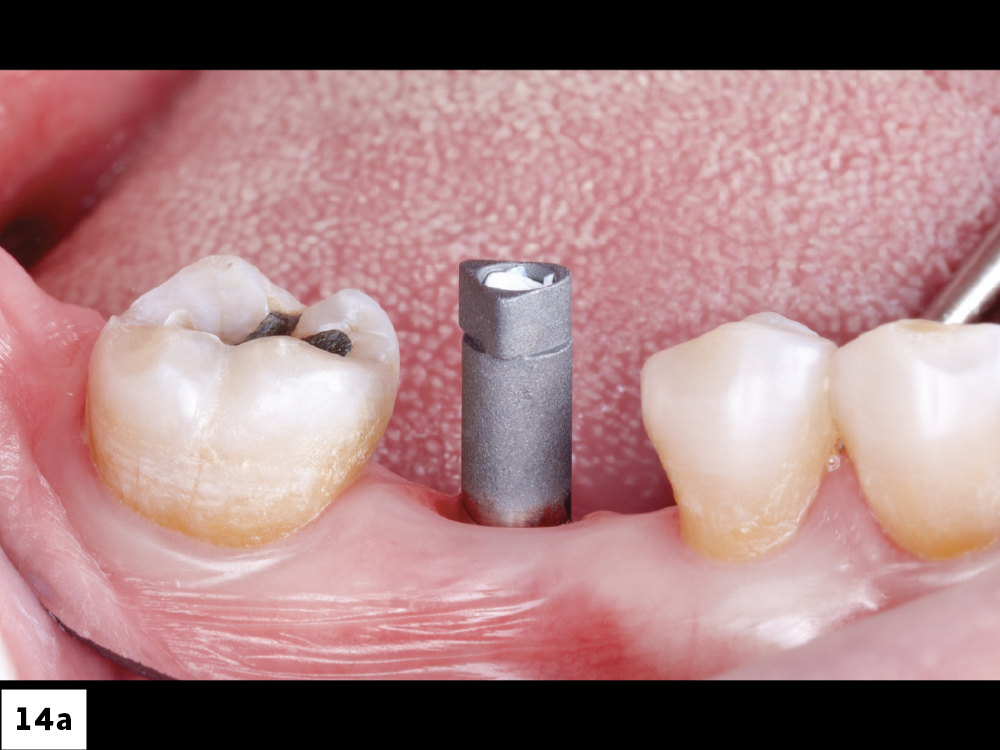

Glidewell HT Implant Titanium Scan Body Placement

Radiograph to Confirm Proper Seating of Scan Body

Figures 14a, 14b: A Glidewell HT Implant Titanium Scan Body (Glidewell Direct) was placed, and proper seating was confirmed with a radiograph. Completely seating the scan body is important. If the scan body is not properly seated, the final restoration will not seat either. Make sure the scan body is screwed into the implant connection and hand-tightened.